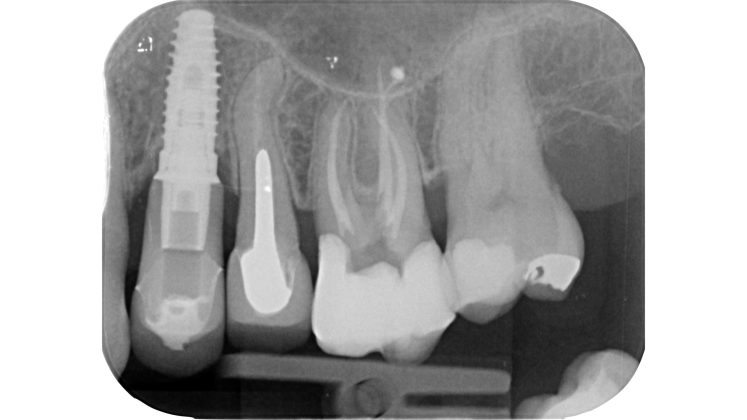

Devono essere valutate con molta attenzione la posizione dell’elemento in arcata e la sua inclinazione (Figure 6-7), l’entità e la posizione del processo carioso se presente, gli eventuali restauri posizionati sul dente e i rapporti con il parodonto: tutte queste considerazioni permetteranno al clinico di capire innanzitutto la mantenibilità e la possibilità di isolare mediante diga di gomma il dente. L’interpretazione degli esami radiografici consentirà inoltre di valutare alcuni parametri preoperatori di notevole importanza:

- qualità dei restauri posizionati sull’elemento dentale ed eventuali infiltrazioni secondarie;

- presenza di radiotrasparenze periradicolari o periapicali;

- difetti ossei di origine parodontale;

- aspetto della camera pulpare e del sistema canalare;

- anatomia radicolare e canalare;

- presenza di pregresse terapie canalari e valutazione della qualità delle stesse;

- presenza o sospetto di riassorbimenti interni o esterni;

- presenza o sospetto di perforazioni e fratture.

Un’attenta analisi di questi dati clinici e radiografici consentirà al clinico di ridurre notevolmente il rischio di errori grossolani in questa delicata fase del trattamento.